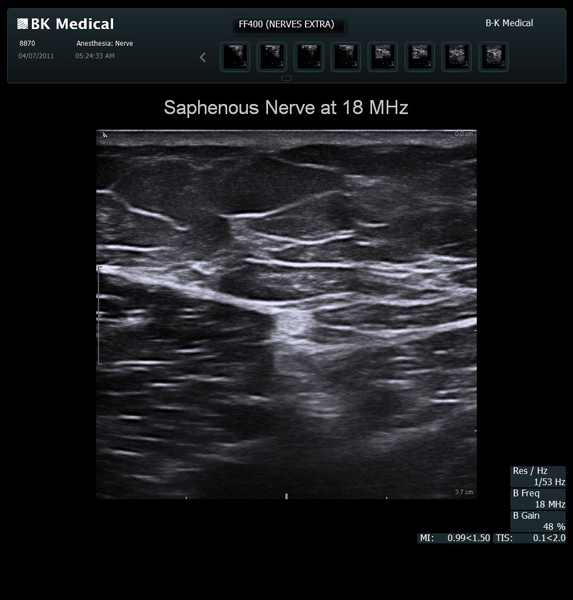

The Flex Focus 400 exp ultrasound system offers premium image quality with fast frame rates for excellent temporal resolution. The system features Automatic Mode Adjustment (AMA) to optimize high resolution B-Mode Imaging when changing modes and depth.

Transducers Designed for Guidance

BK Medical offers high-frequency linear transducers, imaging from 18-2 MHz for upper and lower extremities, and curved array abdominal transducer 8820e for special deep nerves or paravertebral/spinal applications. Our transducers provide superb detail that makes it easy to see your needle during procedures.